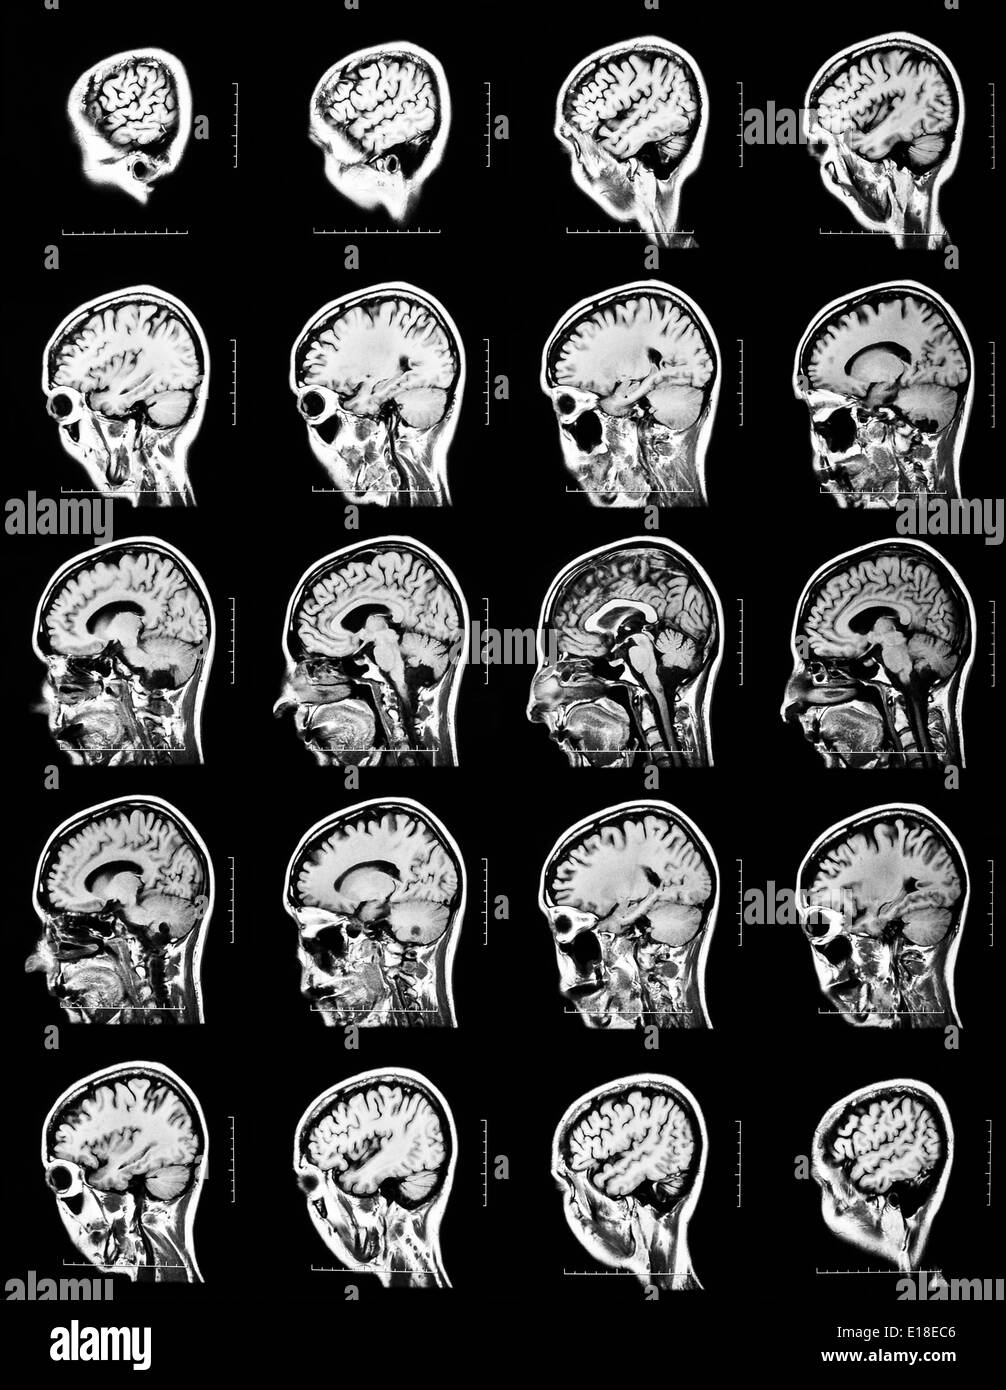

Séquence des sections verticales d'un cerveau humain - IRM Banque D'Imageshttps://www.alamyimages.fr/image-license-details/?v=1https://www.alamyimages.fr/sequence-des-sections-verticales-d-un-cerveau-humain-irm-image69643062.html

Séquence des sections verticales d'un cerveau humain - IRM Banque D'Imageshttps://www.alamyimages.fr/image-license-details/?v=1https://www.alamyimages.fr/sequence-des-sections-verticales-d-un-cerveau-humain-irm-image69643062.htmlRFE18EC6–Séquence des sections verticales d'un cerveau humain - IRM

La section horizontale d'un cerveau humain - IRM Banque D'Imageshttps://www.alamyimages.fr/image-license-details/?v=1https://www.alamyimages.fr/la-section-horizontale-d-un-cerveau-humain-irm-image69643079.html

La section horizontale d'un cerveau humain - IRM Banque D'Imageshttps://www.alamyimages.fr/image-license-details/?v=1https://www.alamyimages.fr/la-section-horizontale-d-un-cerveau-humain-irm-image69643079.htmlRFE18ECR–La section horizontale d'un cerveau humain - IRM